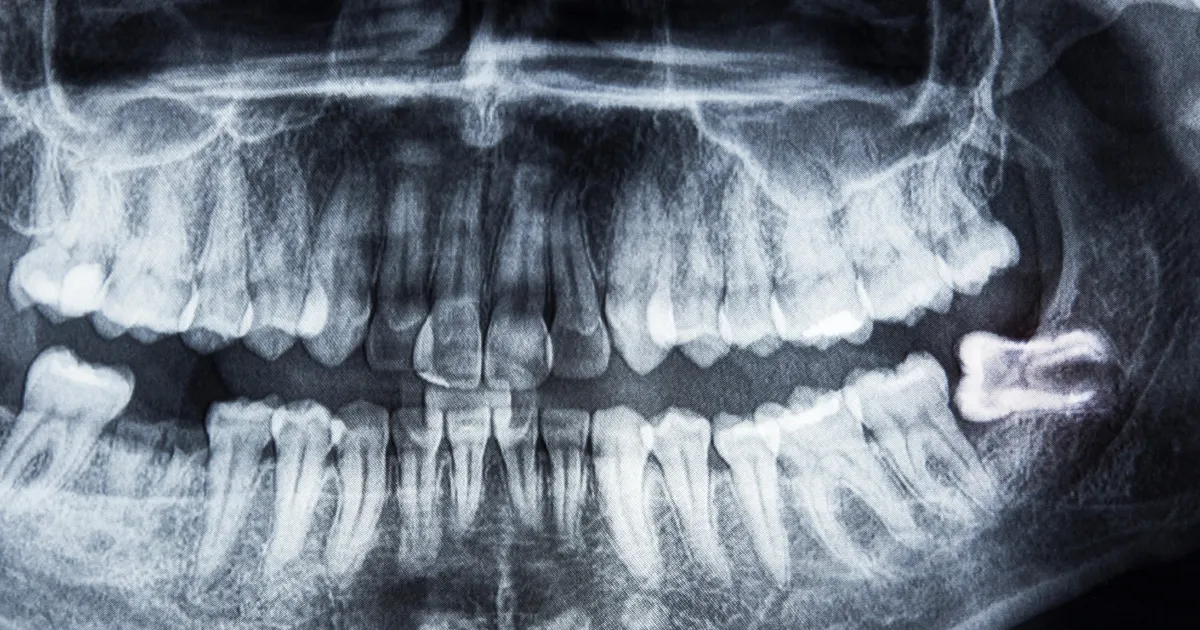

親知らずのタイプ

親知らずの状態は、次のようなタイプに分類されます。

- 生えているタイプ

- 斜めに生えているタイプ

- 完全に歯茎に埋まっているタイプ

順番に解説します。

生えているタイプ

親知らずが完全に歯ぐきの外に出ている状態で、比較的健康な状態にあります。ただし、ブラッシングが難しい場所にあるため、むし歯になりやすいです。

斜めに生えているタイプ

親知らずが正常にまっすぐ生えず、斜めや横向きに生えることがあります。これにより、隣の歯や歯茎に影響を与え、痛みや炎症を引き起こします。

完全に歯茎に埋まっているタイプ

親知らずが完全に歯茎や骨の中に埋まっている場合、通常は痛みがないことが多いですが、感染のリスクがあるため、定期的なチェックが必要です。